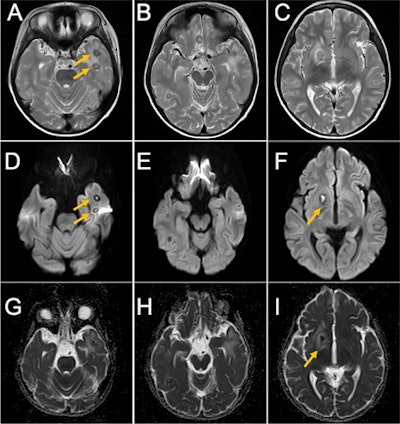

Magnetic resonance imaging (MRI) revealed exacerbation of his brain abscess and circumferential swelling. The patient was transferred to another hospital, and placed on the same course of antibiotic treatment, the authors wrote.

At the new hospital, the boy underwent a whole-body MRI to identify the fungus and source of infection. The MRI revealed several lesions in his frontal lobe, basal ganglia, thalamus, and bilateral temporal lobes. Due to these findings, clinicians suspected a blood-based infection due to multiple brain abscesses, they wrote.

One month after his teeth were pulled, the boy underwent an MRI that revealed that the brain abscess was still there but noticeably reduced. On November 17, he was discharged from the hospital.